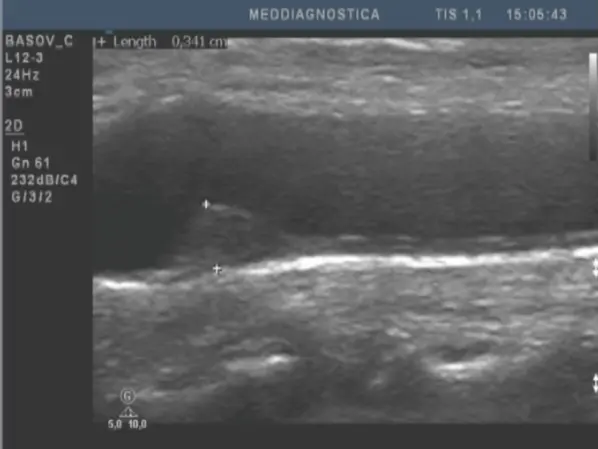

Найдоступніший спосіб діагностики і самий ефективний – це атеросклеротичний тест (розробка клініки «Меддіагностика»). Він дозволяє протягом декількох хвилин визначити наявність атеросклерозу і його стадію. Ми виявляємо наявність атеросклеротичних бляшок, визначаємо ступінь звуження судин серця, а також – найбільш ранні прояви атеросклерозу – потовщення внутрішнього шару судин. На цьому етапі ми можемо ефективно впливати на процеси розвитку атеросклерозу. Часто вдається стабілізувати процес або навіть зменшити його прояви.

Нижче наведені приклади візуалізації атеросклеротичного ураження судин.